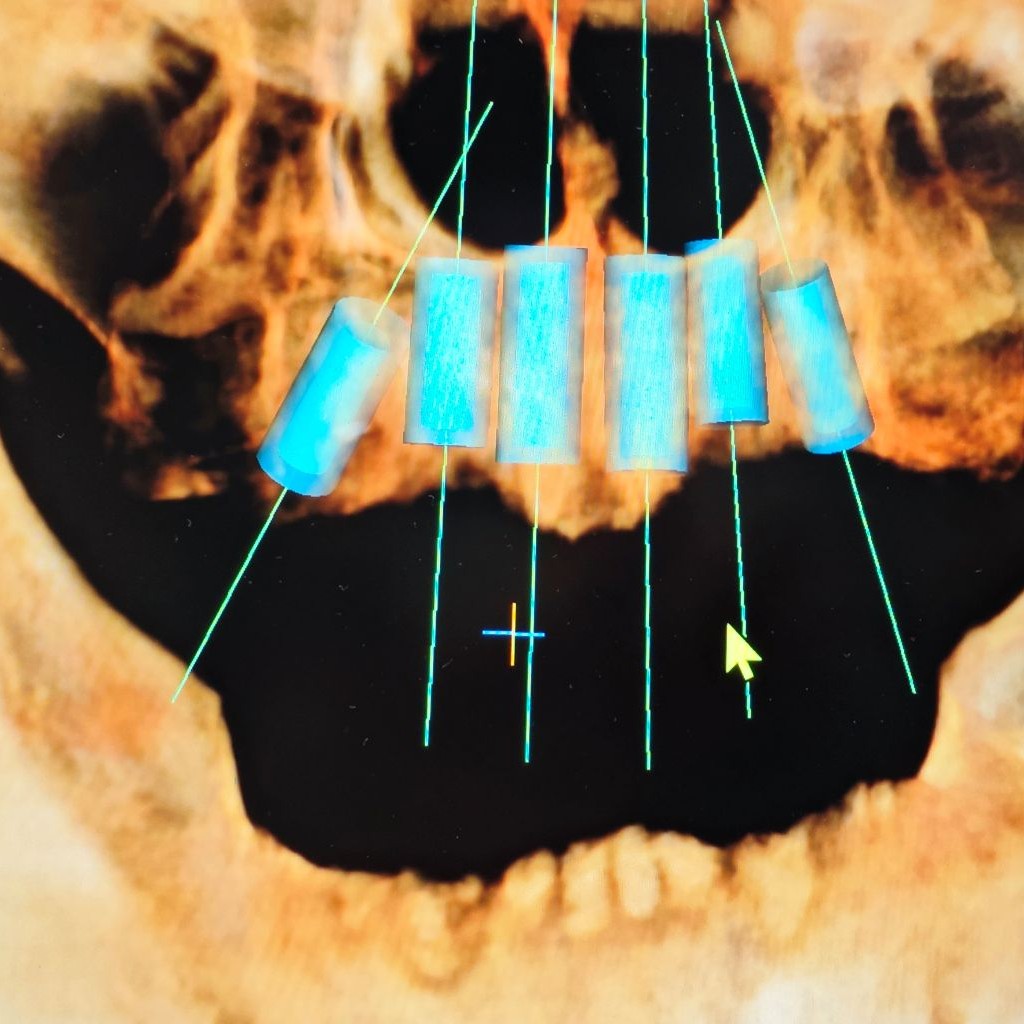

Дигиталната радиографија во стоматологијата се однесува на употребата на технологија за дигитално снимање и складирање на снимки на забите со Х-зраци. Тој стана широко прифатен метод во стоматолошките ординации, заменувајќи ги традиционалните рендгенски снимки базирани на филм. Дигиталната радиографија нуди неколку предности во однос на конвенционалната радиографија, вклучувајќи подобрен квалитет на сликата, намалена изложеност на радијација и зголемена удобност и за стоматолошките професионалци и за пациентите.